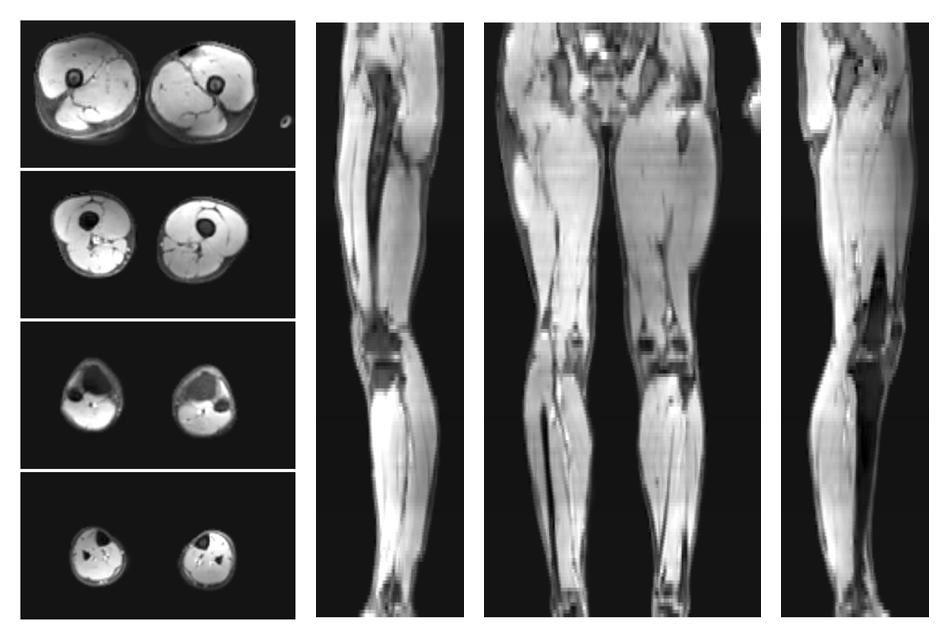

• Water only signal

The water part of the acquired multi-echo spin echo data.